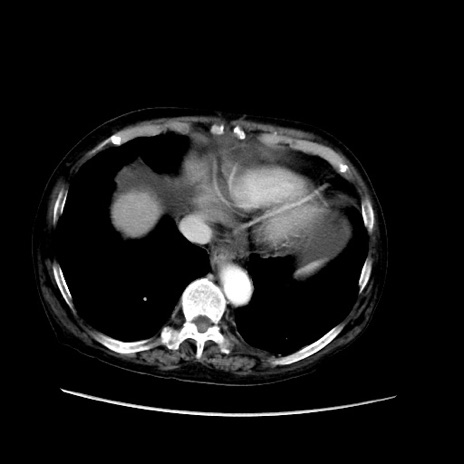

矢状断像